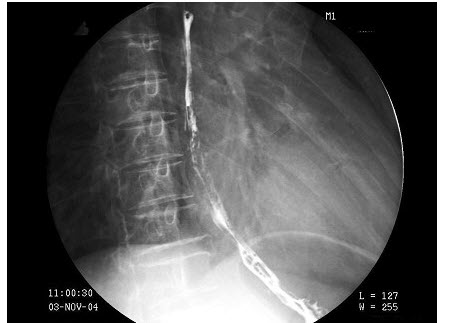

126、单项选择题

椎间盘脱出的部位常见于()

A.C1-2

B.T3-4

C.L1-2

D.C7~T1

E.L5~S1